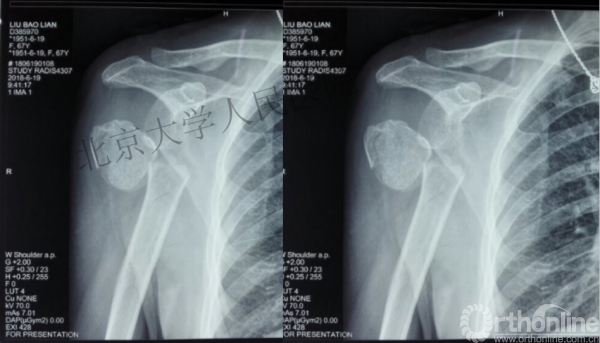

内侧皮质粉碎,低位外科颈骨折,肱骨头-干角维持困难。

术后复位丢失,肱骨头内翻畸形。

能否该偏心固定(钢板)为髓内固定,增加力臂?

早知今日,何必当初?

此时对比髓内钉是不是有很大优势?